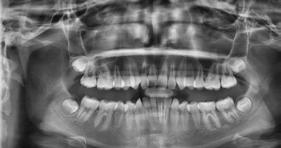

Estudios radiográficos de inicio

En la radiografía lateral de cráneo se observa un crecimiento hiperdivergente y la clase II esquelética con un Witts de 2 mm (Figura 7). En panorámica, 31 dientes permanentes presentes con terceros molares impactados y ausencia de OD 48 (Figura 8).